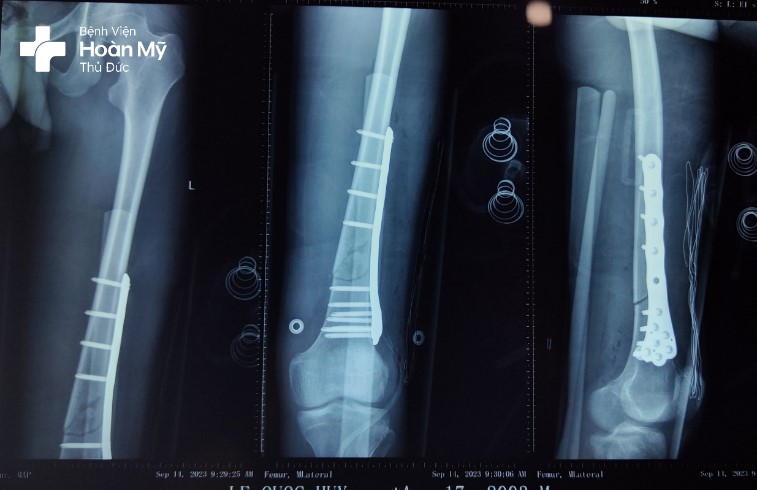

Hình chụp X-quang sau mổ: kết hợp xương nẹp vít